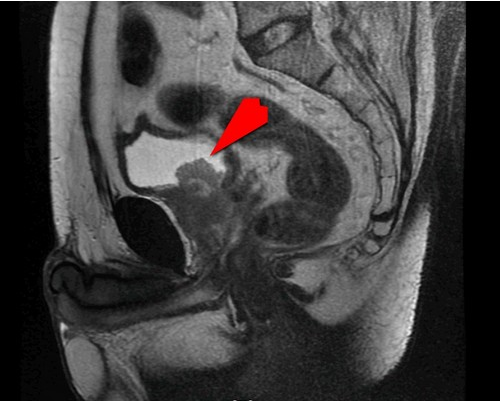

▲核磁共振影像中紅色箭頭所指,顯示病人攝護腺腫瘤已侵犯膀胱。(江元宏主任提供)

一位63歲病人三年前被診斷出攝護腺癌時已是第4A期,不但有淋巴轉移,腫瘤也侵犯到膀胱,經採用賀爾蒙療法(雄性素剝奪治療,ADT)五個月腫瘤變小後,以達文西機器手臂進行淋巴結廓清術與根除性攝護腺切除手術,再追加放射線治療與賀爾蒙療法,病人在接受三線治療下,至今攝護腺特定抗原指數(PSA)仍歸零(低於最低偵測值)。